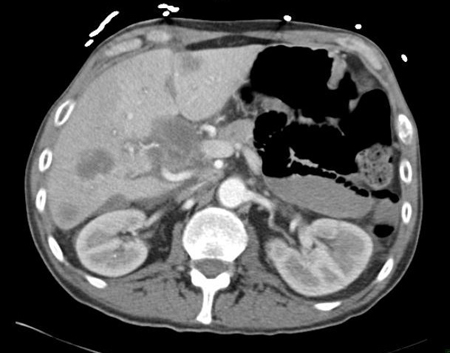

Tomografia computadorizada (TC) abdominal com contraste intravenoso, revelando diversas lesões hepáticas com realce nos dois lobos hepáticos; a biópsia percutânea de uma lesão do lobo direito revelou adenocarcinoma

Do acervo pessoal do Dr. D. Cosgrove